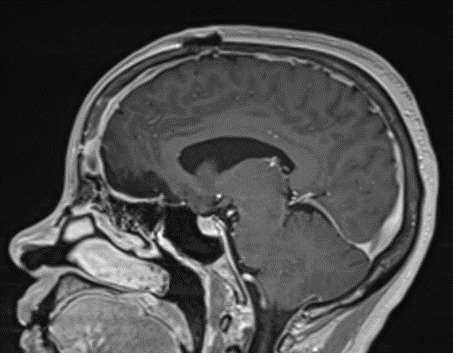

This is a 49-year-old otherwise healthy female who presented with bifrontal and retro-orbital headaches, behavioral changes, and forgetfulness. Symptoms have been progressively worsening over the past month. Her neurologic exam revealed a pronator drift, otherwise was unremarkable. MRI brain demonstrated a large extra-axial homogeneously enhancing mass of the anterior cranial fossa, resulting in significant mass effect and vasogenic edema (Figure 1a and 2a). Imaging was most consistent with a planum sphenoidale meningioma. She was referred to Dr. Xavier Gaudin for neurosurgical evaluation.

Figure 2a – Preoperative MRI demonstrating an extra-axial lesion with surrounding vasogenic edema and mass effect on the frontal lobes.